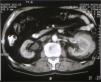

At admission physical examination was unremarkable. Laboratory data showed hematocrit 34.5 %, hemoglobin 11 g/dl, white blood cells 5950/ml with normal differential count, platelets 161000/ml, and an erythrocyte sedimentation rate of 100 mm/h. Blood coagulation was normal. Urinalysis revealed normal sediment and proteinuria 1.2 g/24 h. Serum urea was 70 mg/dl, serum creatinine 2.2 mg/dl, and creatinine clearance 45 ml/min. The total serum proteins were 9.6 g/dl, albumin 4.1 g/dl, and gammaglobulin 3.5 g/dl (with a monoclonal peak). The serum immunoglobulin levels measured by nephelometry were IgM 4640 mg/dl (normal 38-231 mg/dl), IgG 858 mg/dl (normal 650-1700 mg/dl), and IgA 168 mg/dl (normal 103-568 mg/dl), kappa 641 mg/dl (normal 170-370 mg/dl), lambda 106 mg/dl (normal 90-210 mg/dl). Monoclonal IgM kappa was detected in the serum by immunofixation. Serum cryoglobulin was negative and Bence-Jones proteinuria was positive. Other laboratory data showed C reactive protein 4.9 mg/dl, beta 2-microglobulin 4.9 mg/l, lactate dehydrogenase 286 U/l, serum calcium 9.9 mg/dl, and serum phosphate 3.2 mg/dl. EBV and HCV were negative. Abdominal ultrasound examination showed a solid mass in the left kidney. A skeletal roentgenogram and a bone scan revealed no abnormalities. A thoracoabdominal CT revealed a 7 cm mass located in the midportion of the left kidney (Fig. 1). There was no evidence of lymphadenopathy. A bone marrow aspirate showed a normocellular patter and revealed 12.5 % atypical plasma cells. Bone marrow flow cytometry showed 3 % polyclonal T lymphocytes and 1 % polyclonal B lymphocytes. The plasma cells were CD38++, CD138-, CD19+, CD45+, CD56-, CD117-, and monoclonal kappa.

Figure 1. CT showing tumoral growth through the renal cortex of the left kidney.